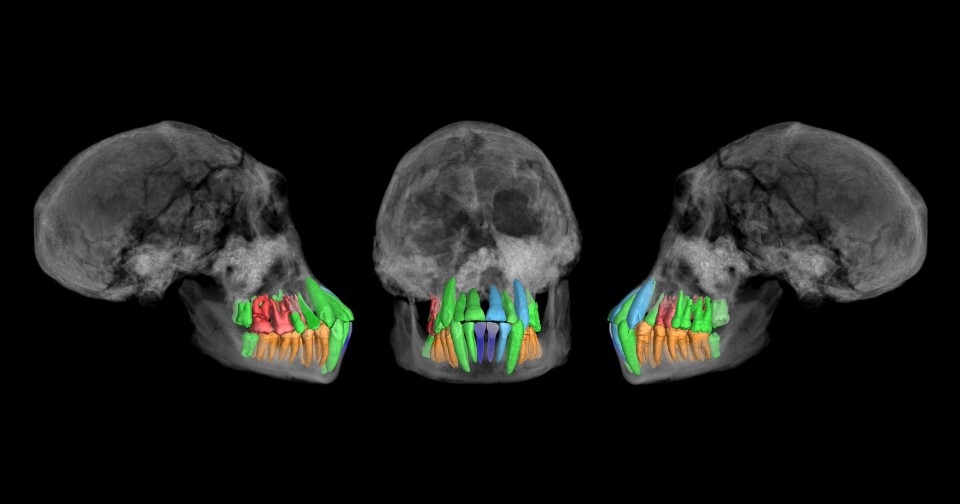

В новой работе Христоф Цолликофер (Christoph Zollikofer) из Цюрихского университета совместно с коллегами из Грузии, Франции, Швейцарии и Южной Кореи представил результаты дальнейших исследований останков из Дманиси. На этот раз они сосредоточили свое внимание на зубах молодого индивида, от которого до наших дней сохранились и череп (D2700), и нижняя челюсть (D2735), чтобы выяснить, насколько сильно различались темпы формирования и развития постоянного зубного ряда у ранних людей прямоходящих, современных людей (H. sapiens) и человекообразных обезьян: обыкновенных шимпанзе (Pan troglodytes), бонобо (P. paniscus), горилл (Gorilla) и орангутанов (Pongo).

Постоянный зубной ряд индивида из Дманиси представлен как минимум одним антимером каждого типа зубов. Исключение составили лишь первые резцы нижней челюсти. Третьи моляры этого человека были практически полностью сформированы. Это говорит о том, что он умер незадолго до наступления зубной зрелости.

Ученые исследовали останки с помощью синхротронной фазово-контрастной микротомографии (PPC-SRμCT), а затем прибегли к методам виртуальной гистологии, чтобы получить полную информацию о наиболее хорошо сохранившихся зубах. Среди прочего, это позволило определить, что на момент смерти этому индивиду 11,36 ± 0,65 года. По оценкам палеоантропологов, закрытие верхушек корней третьих моляров у него произошло бы через 1,3–1,5 года. Следовательно, полная зубная зрелость наступала примерно в 12–13,5 года.

Что касается индивида из Дманиси, то примерно до четырех лет его постоянный зубной ряд формировался по траектории, характерной для современных людей. Однако скачок развития произошел раньше — примерно в 5,3 года, а к восьмилетнему возрасту траектория развития стала похожа на шимпанзиную. Но зубная зрелость наступала, по-видимому, немного позже — к 12–13,5 года. Исследователи заключили, что для онтогенеза зубов у архаичного человека из Дманиси были характерны прогрессивные черты, свойственные для современных людей, так и примитивные черты, которые сохраняются у других приматов. Так, подобно современным людям, большинство задних зубов (кроме первых моляров) у него прорезались с задержкой по сравнению с передними (резцами и клыками), а также был большой интервал между временем прорезания первых, вторых и третьих моляров, что не характерно для упомянутых нечеловеческих приматов.